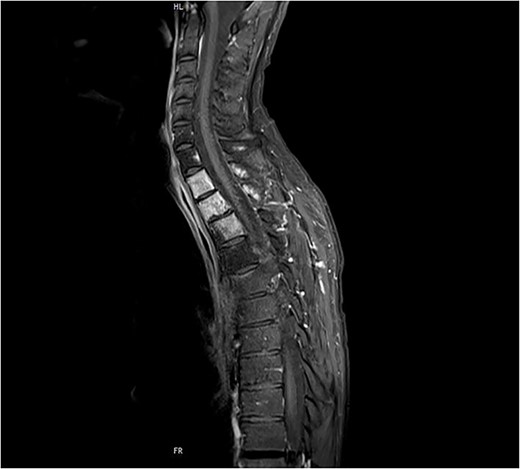

Despite the definitive chemoradiation therapy, a locally progressive tumor without evidence of distant metastasis was detected 2 months later in an MRI associated with the infiltration of Th1–3 and invasion of the first and second left thoracic root without evidence of a myelon compression (Figs 1 and 2).

Preoperative sagittal MRI (STIR) image of patient No. 2 depicting active tumor invasion of T1, T2 and T3 as well as pathological hypodense C7 and Th4 vertebral bodies.

Transversal MRI STIR-images of patient No. 2 with Th1 (a), Th2 (b) and Th3 (c).